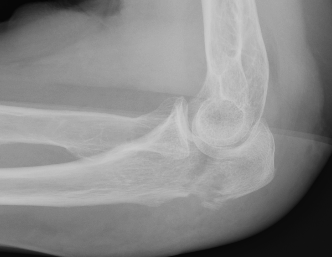

Mayo Classification

A: Non comminuted

B: Comminuted

| Type I | Type II | Type III |

|---|---|---|

| Minimally displaced | Displaced | Trans-olecranon fracture dislocation |

| 10% | 85% | 5% |